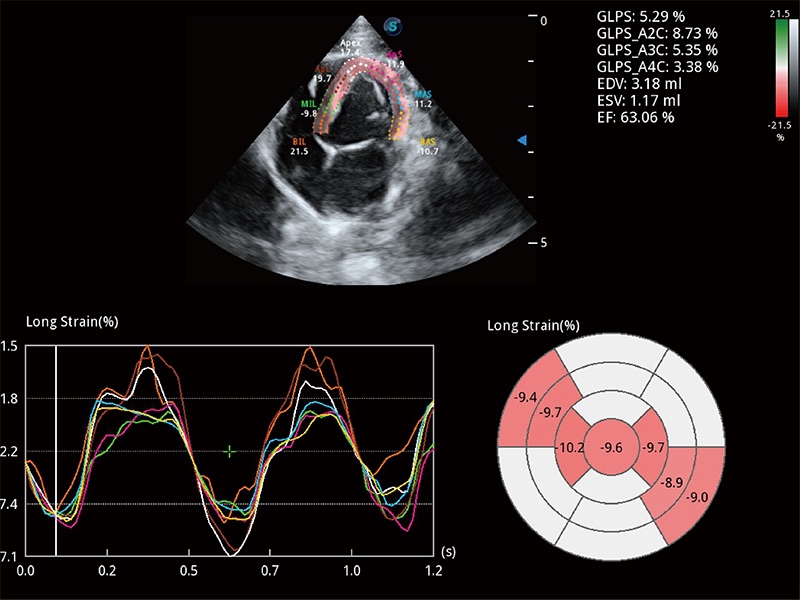

• MQA 心肌定量分析

通过心肌识别技术与二维斑点追踪技术相结合,对心脏的超声图像进行量化分析。计算心肌17个节段的应变、应变率、速度、位移等,并通过牛眼图的形式进行呈现。